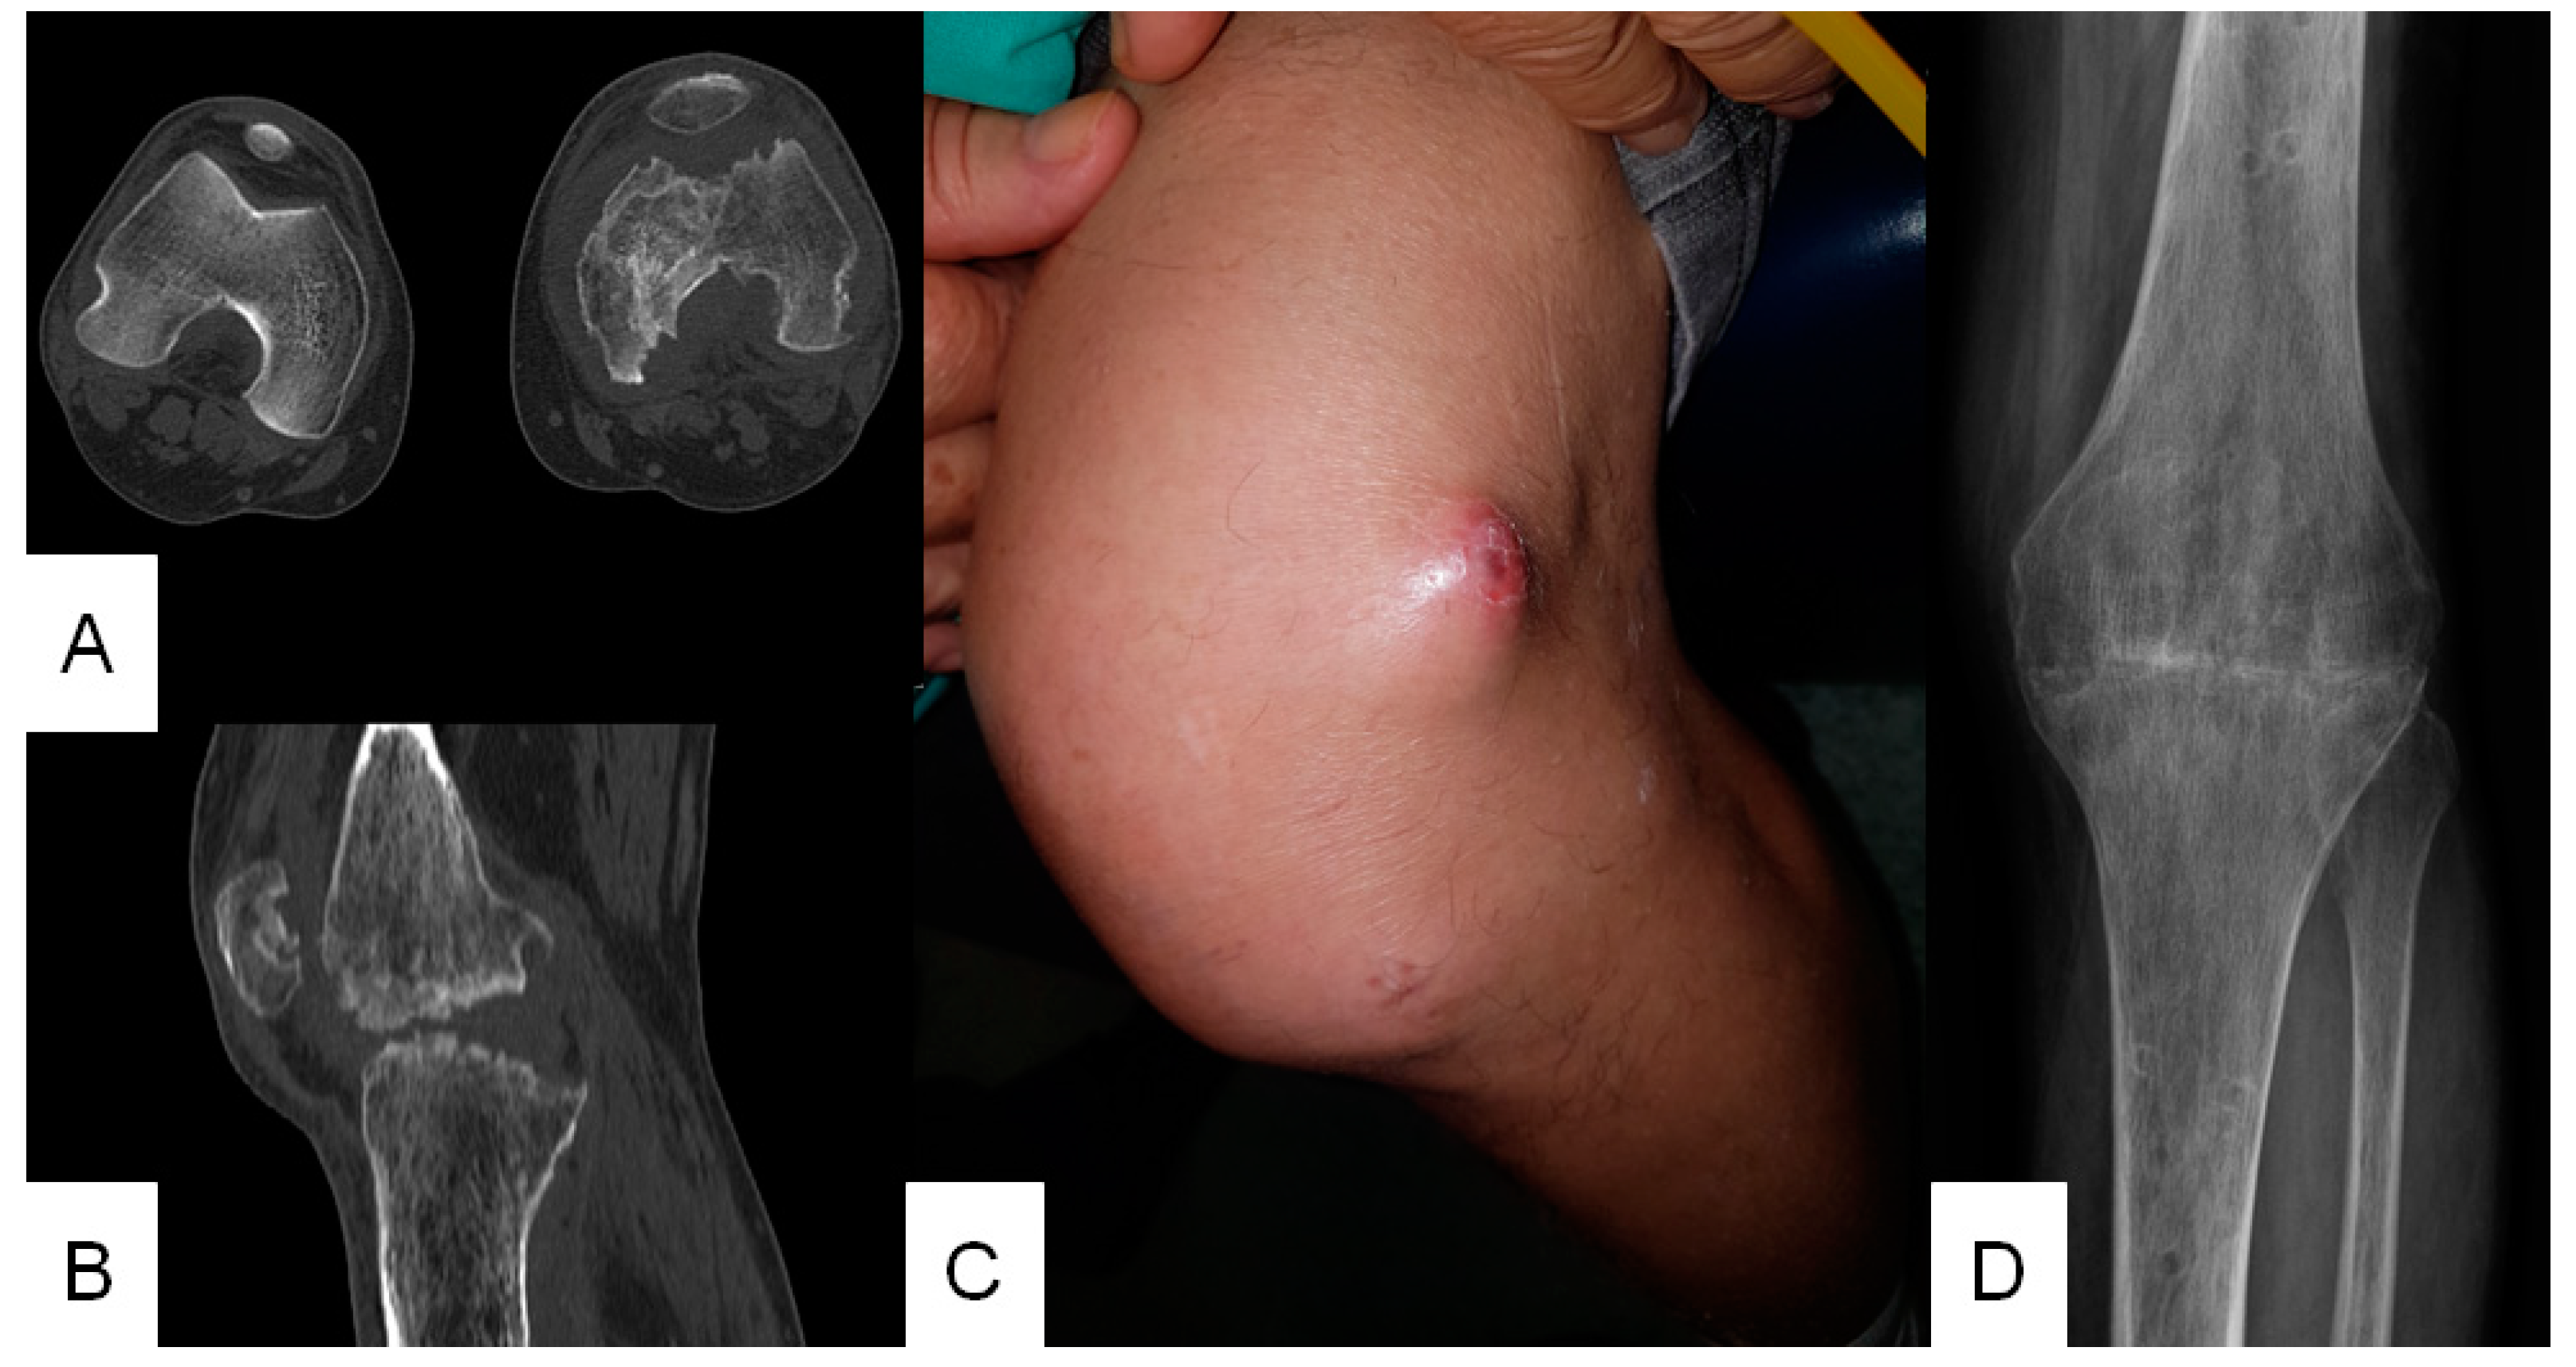

2.1. Patient 1